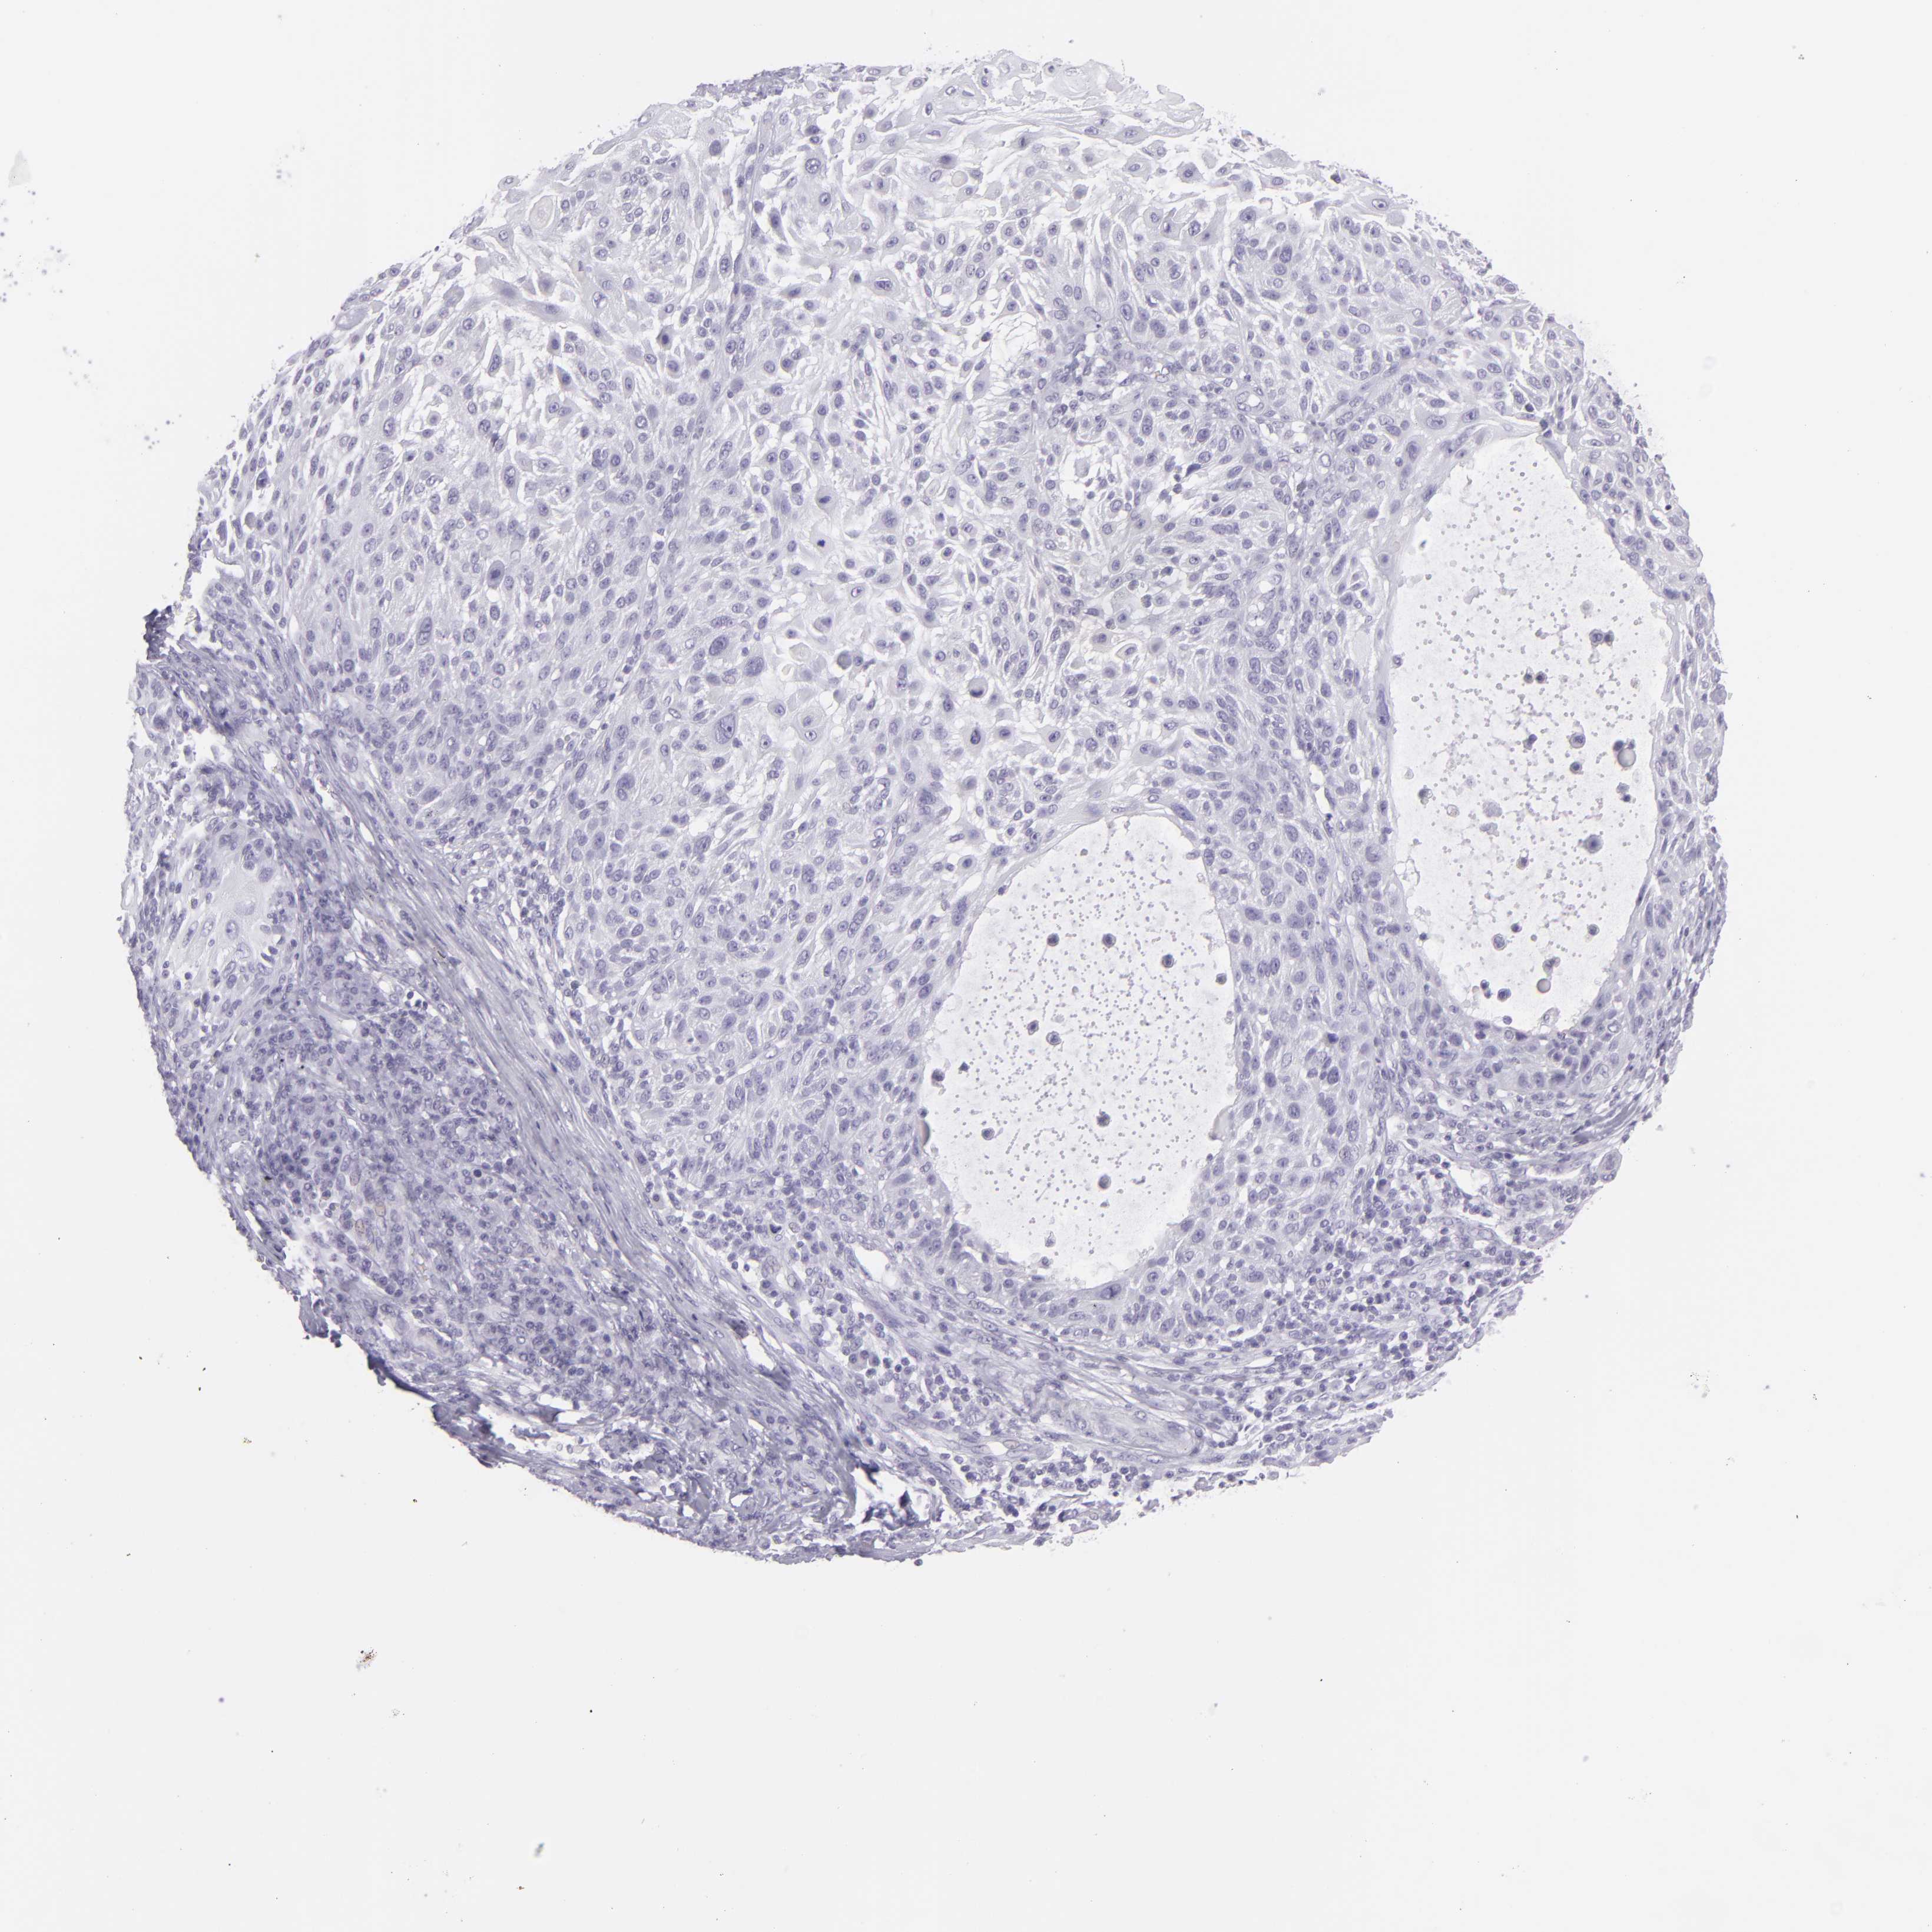

Basal cell and squamous cell cancer

SKIN CANCER - Protein expressioni

A mouse-over function shows sample information and annotation data. Click on an image to view it in a full screen mode. Samples can be filtered based on level of antibody staining by selecting one or several of the following categories: high, medium, low and not detected. The assay and annotation is described here.

Each image is clickable and will lead to virtual microscopy that enables deeper exploration of all samples and also displays staining intensity scores, fraction scores and subcellular localization as well as patient and tissue information for each sample.

Antibody CAB002165

Staining

High

Intensity

Strong

Quantity

>75%

Location

Nuclear

Squamous cell carcinoma, NOS

Basal cell carcinoma